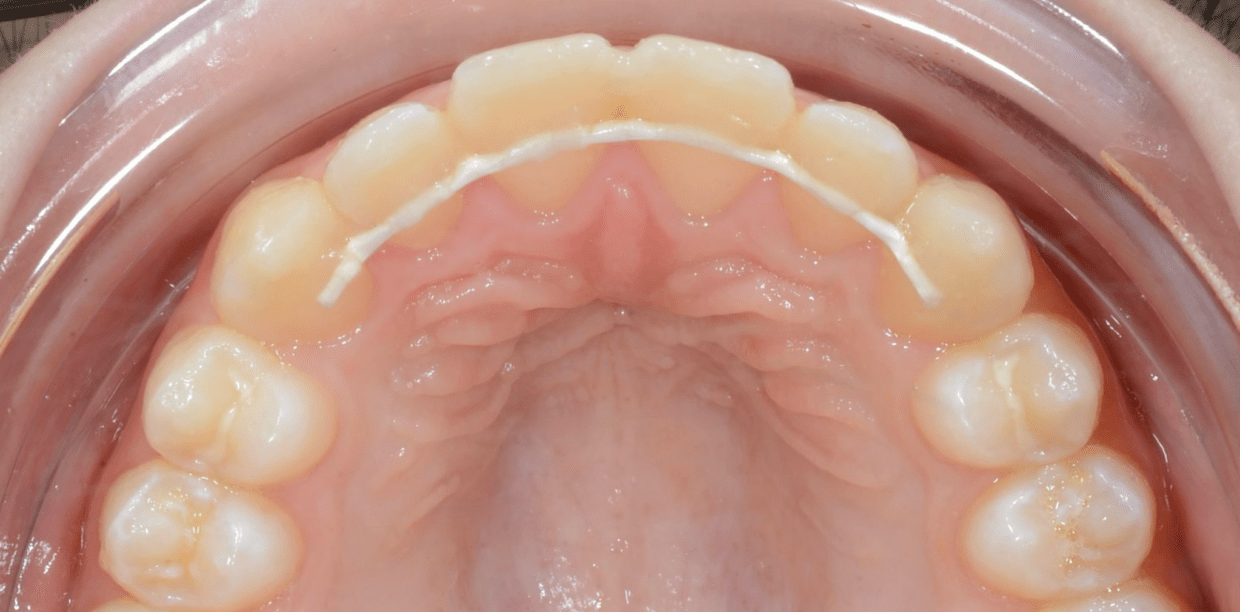

Cas cliniques

Simple - A2

Simple - A2

Simple - A2

Simple - A2